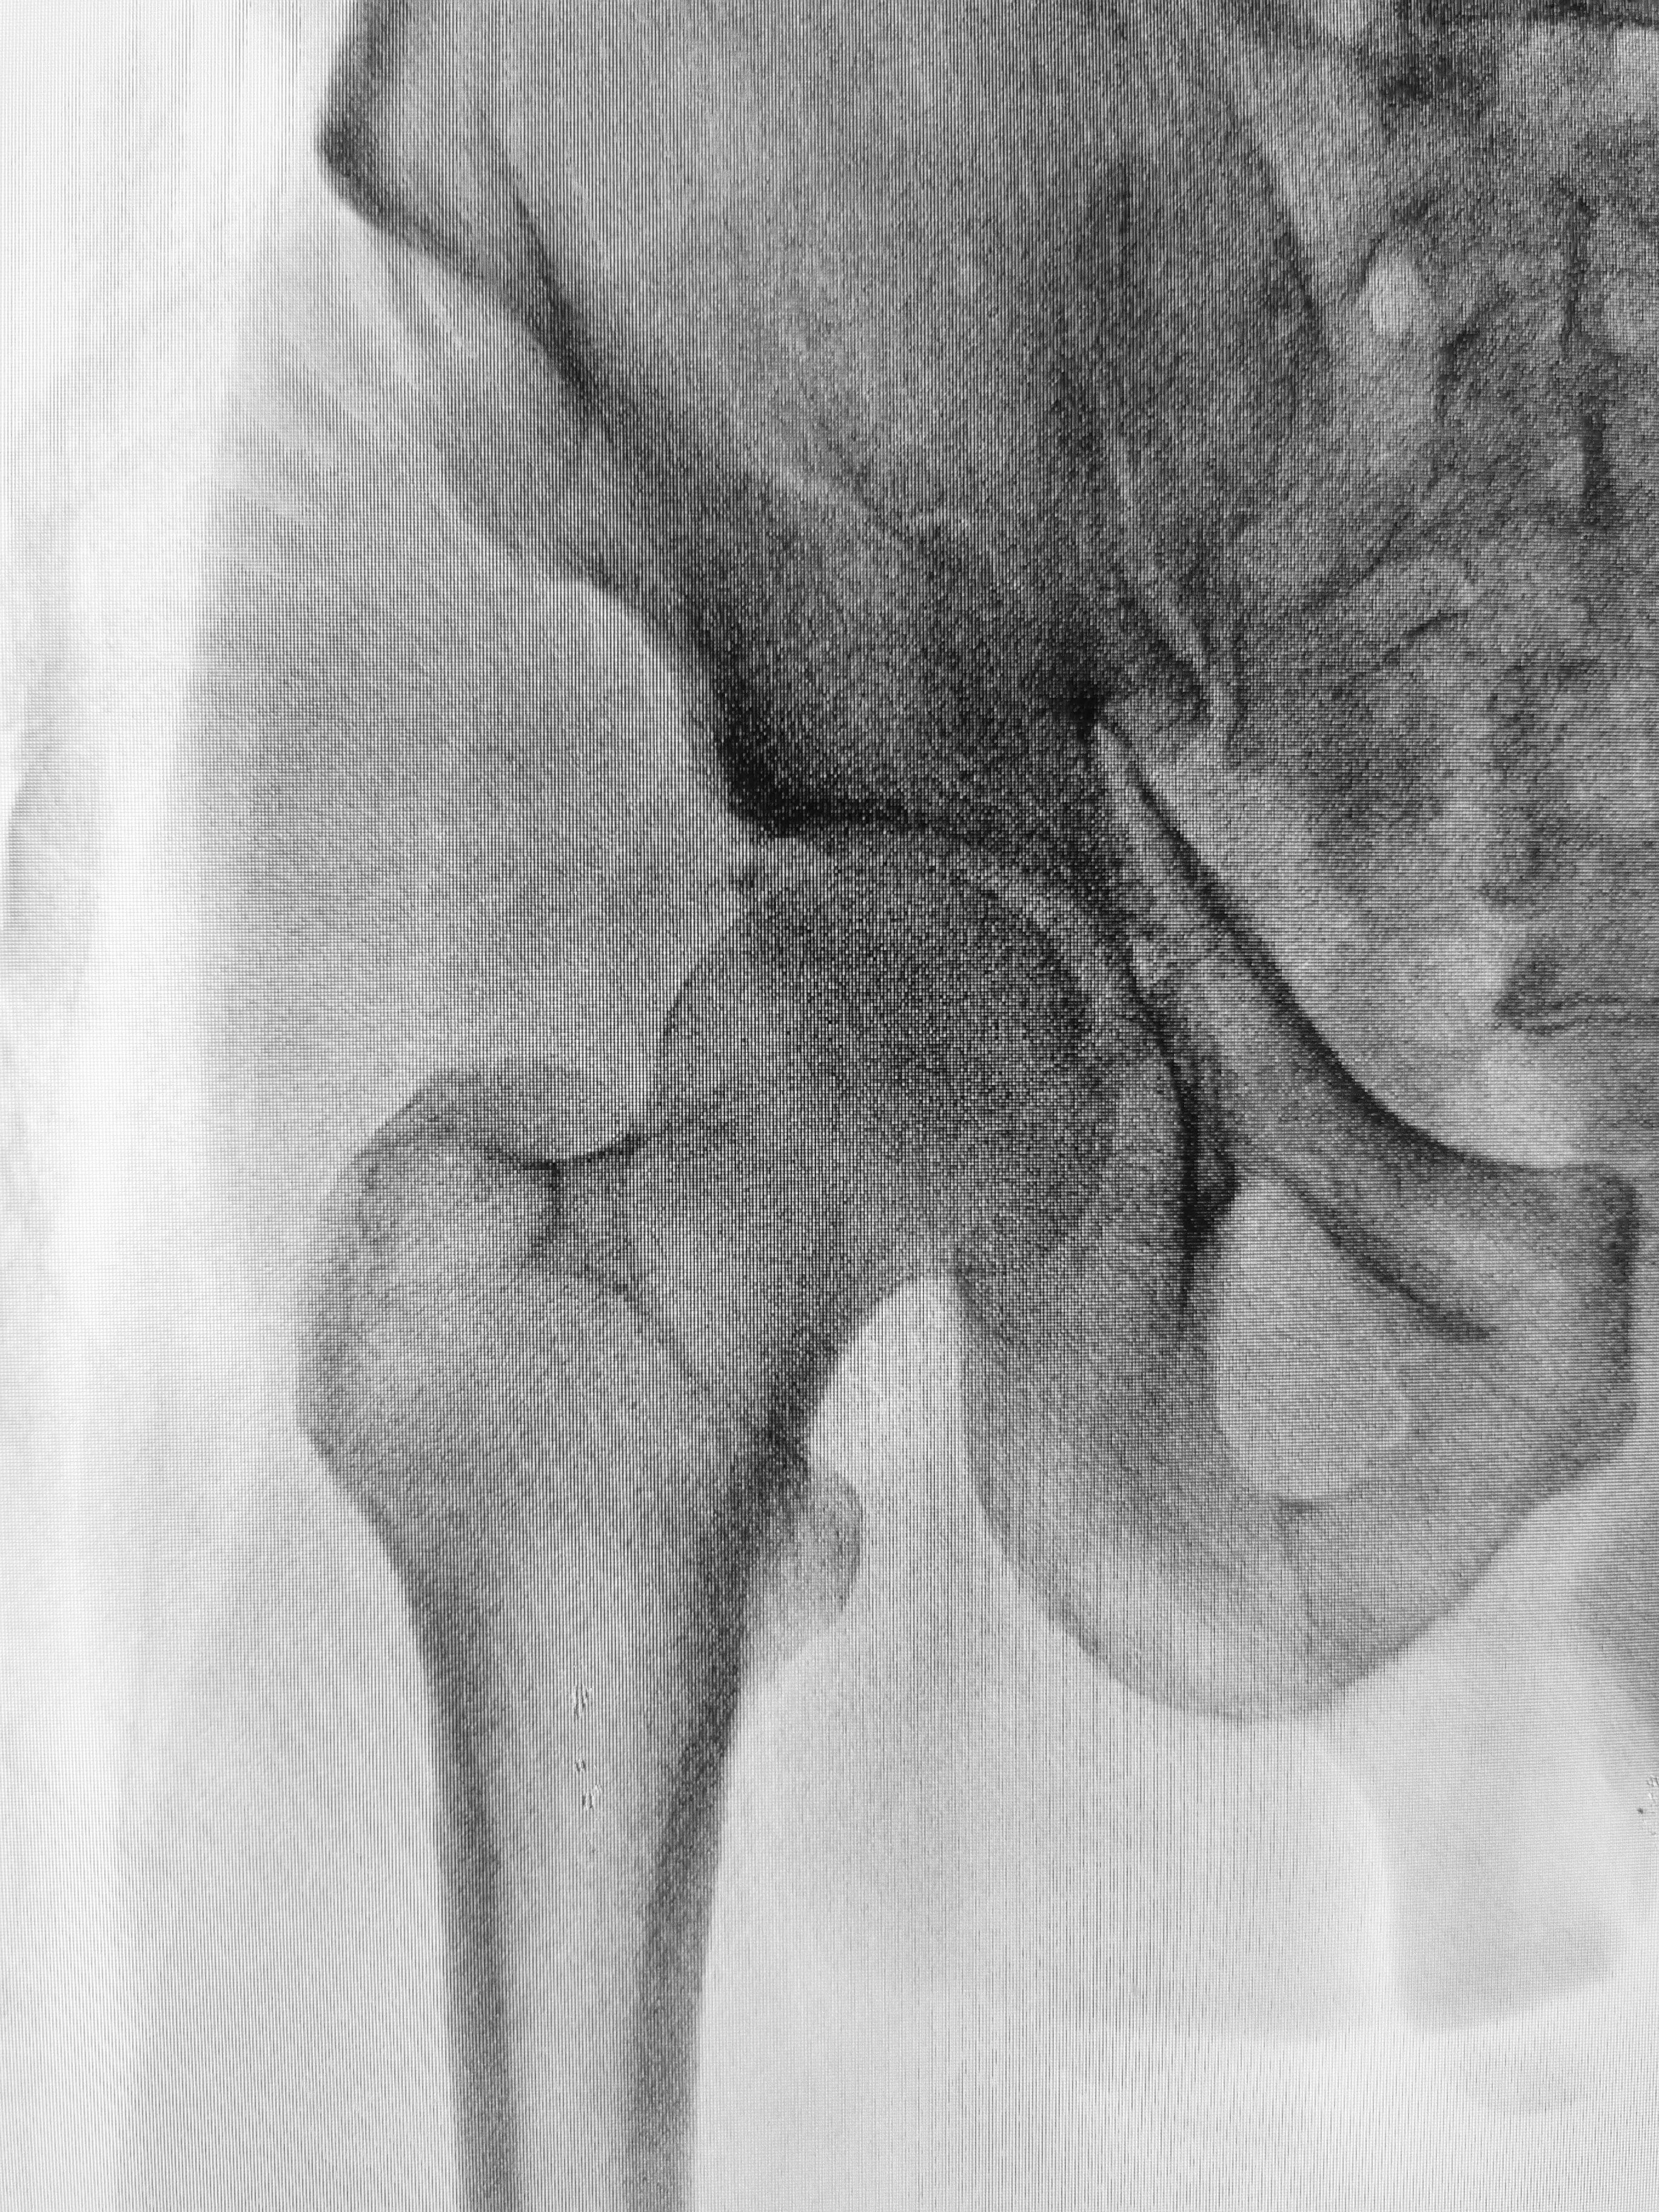

Según explica, la cirugía a la que los ingenieros se están sometiendo para lucir más altos, consiste en romper los huesos de los muslos, específicamente del fémur, e insertar clavos de metal.

Estos clavos, a su vez, se van expandiendo todos los días durante tres meses a través de un control remoto.

Esto ayuda a que los huesos se vayan alargando lentamente y que estos vayan sanando, lo cual hace que las personas luzcan más altas, por lo cual los ingenieros de Amazon, Google, Meta y Microsoft están pagando.